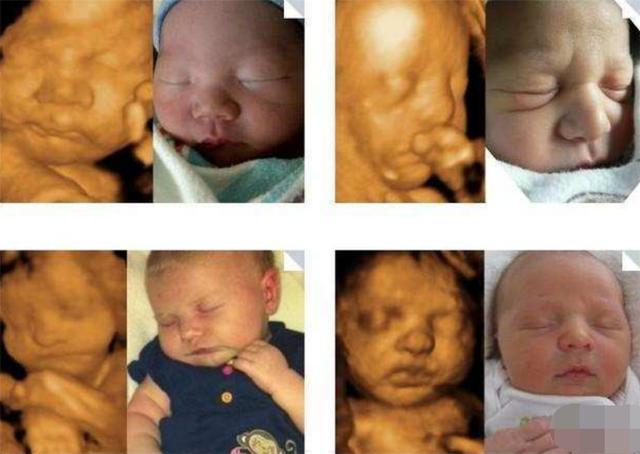

大概在五个月的时候,在老公的陪同下张女士去做了产检,通过仪器的照片可以看到宝宝的样子,没想到让张女士感到很尴尬,四维照下的宝宝原型毕露,和自己想象的完全不一样。宝宝的鼻子和嘴比较平而且还很小,最关键的是头像看起来不太标准,至于长的像谁看不出来,不过可以肯定的一点是有点丑。

四维照给人感觉和现实不太一样,感觉一点都不真实,只能看到大概的轮廓,而且也是隐隐约约的,张女士本来以为可以看到一个帅气的宝宝,哪怕是稍微可爱一点也可以,结果一点都没让自己满意。反正孩子现在还在发育中,相信将来孩子出生的时候一定不会让自己失望的。

宝宝在发育不全的时候看起来会有点丑,这是正常的情况,毕竟离出生的时间还有些距离,不能长到成熟的样子,通过四维照看到的宝宝也不完全是清晰的,可能会有些偏差,所以看起来会觉得有点丑,不用太放在心上。

角度不一样的时候看到的结果也不同,这是因为四维照从不同的角度把他们合成之后,你才能看到眼前的结果,有时候看到的结果确实是最丑的角度,只能看到一个大概的样子,另外宝宝的环境是在羊水中,也会显得样子模糊。